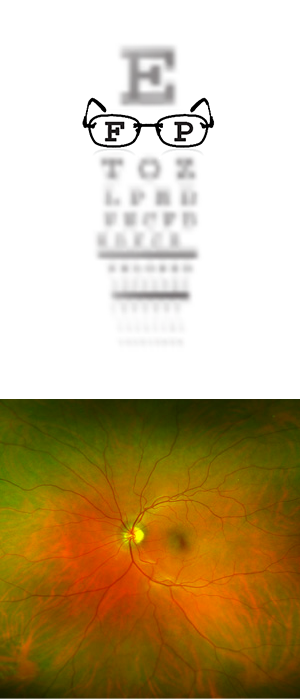

A thorough examination of the eyes at Focus 313 begins with a refraction using the newest technology available in order to precisely correct your vision. Your ocular health will then be examined using state of the art equipment to look for any eye diseases such as glaucoma, macular degeneration, cataracts, ocular allergies and dry eyes.

Focus 313 Eyecare now offers Optomap Retinal Imaging technology! This fast, painless test allows for a comprehensive view of the retina in order to detect eye diseases and life-threatening diseases such as cancer, stroke and cardiovascular disease without dilation.